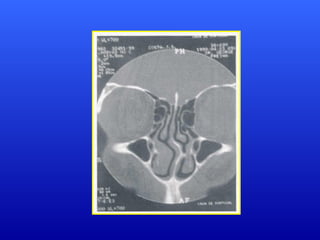

Correlação entre PalatoEscavadoCorrelação entre Palato Escavado e Desvio de Septo Nasal:e Desvio de Septo Nasal: